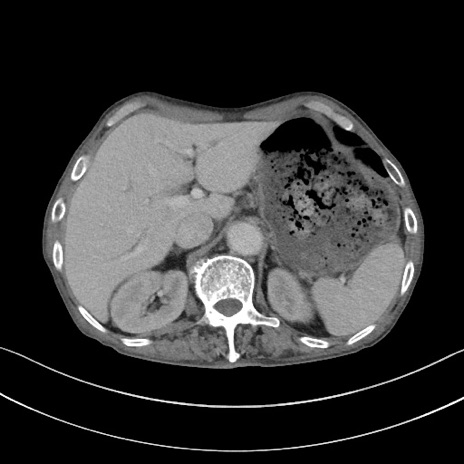

冠状断像

矢状断像